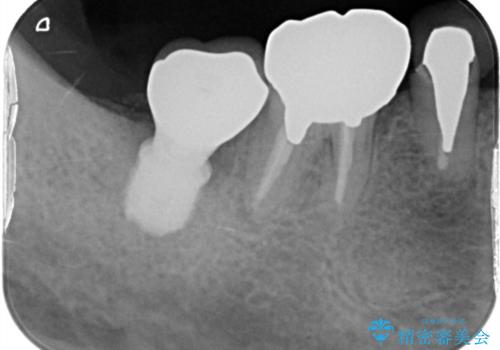

- 食事の度に、歯の中に物がつまるとのことで来院された患者様です。

精密検査を行った結果、歯が折れていたため保存は難しく、インプラント治療になりました。

インプラント治療をすることによってしっかりと噛めるようになりました。